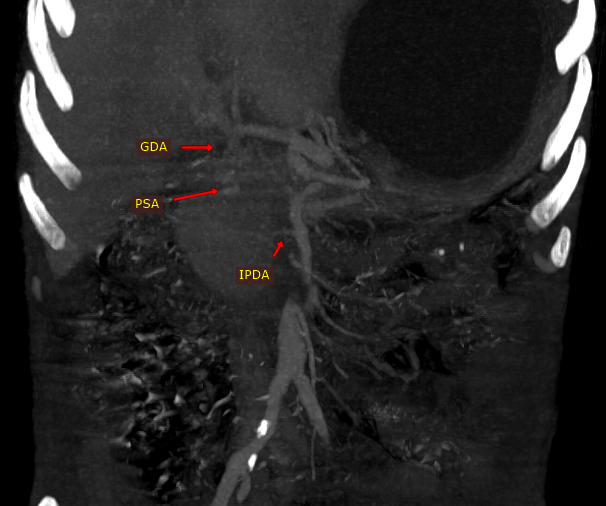

@iRadBIR_Chennai @SRajesh_IR @karananandpara @iRadRock @keithppereira @ChengaziMD @Murthy_CS_ @PulkitRangarh @drochohan I would still trap the aneurysm via SMA. Stenosis is distal to the GDA stump. So it should largely make no difference. It may be vasospasm which may get relieved.

A straightforward GDA Pseudoaneurysm embolization. But Angiogram looks like this, how would you proceed further? #iRad #MedTwitter @SRajesh_IR @karananandpara @iRadRock @keithppereira @ChengaziMD @Murthy_CS_ @lenonjdee @PulkitRangarh @drochohan @ChengaziMD